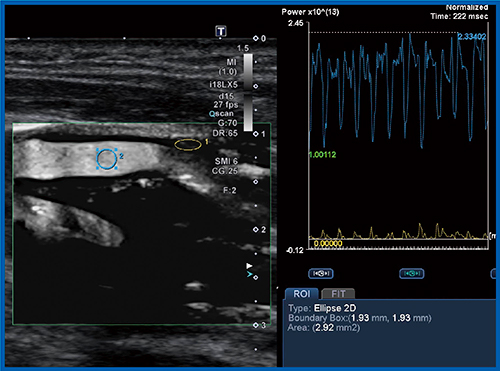

SMI上で,血管内腔とプラークにそれぞれROIを設定し,時間ごとのintensityを見ていくと,収縮・拡張により血管内腔は大きく変動して,プラークもわずかに上下しているのが定量できる(図4)。このことを踏まえると,収縮・拡張を加算して平均化した比を取った値は,血管新生の程度と比例すると考えられる。さらに,SMI上の規則的な信号変化とプラークの病理との相関を見ることで,MESの発生を術前に予知できる可能性がある。

図4 SMIによる血管内腔とプラークのintensityの定量